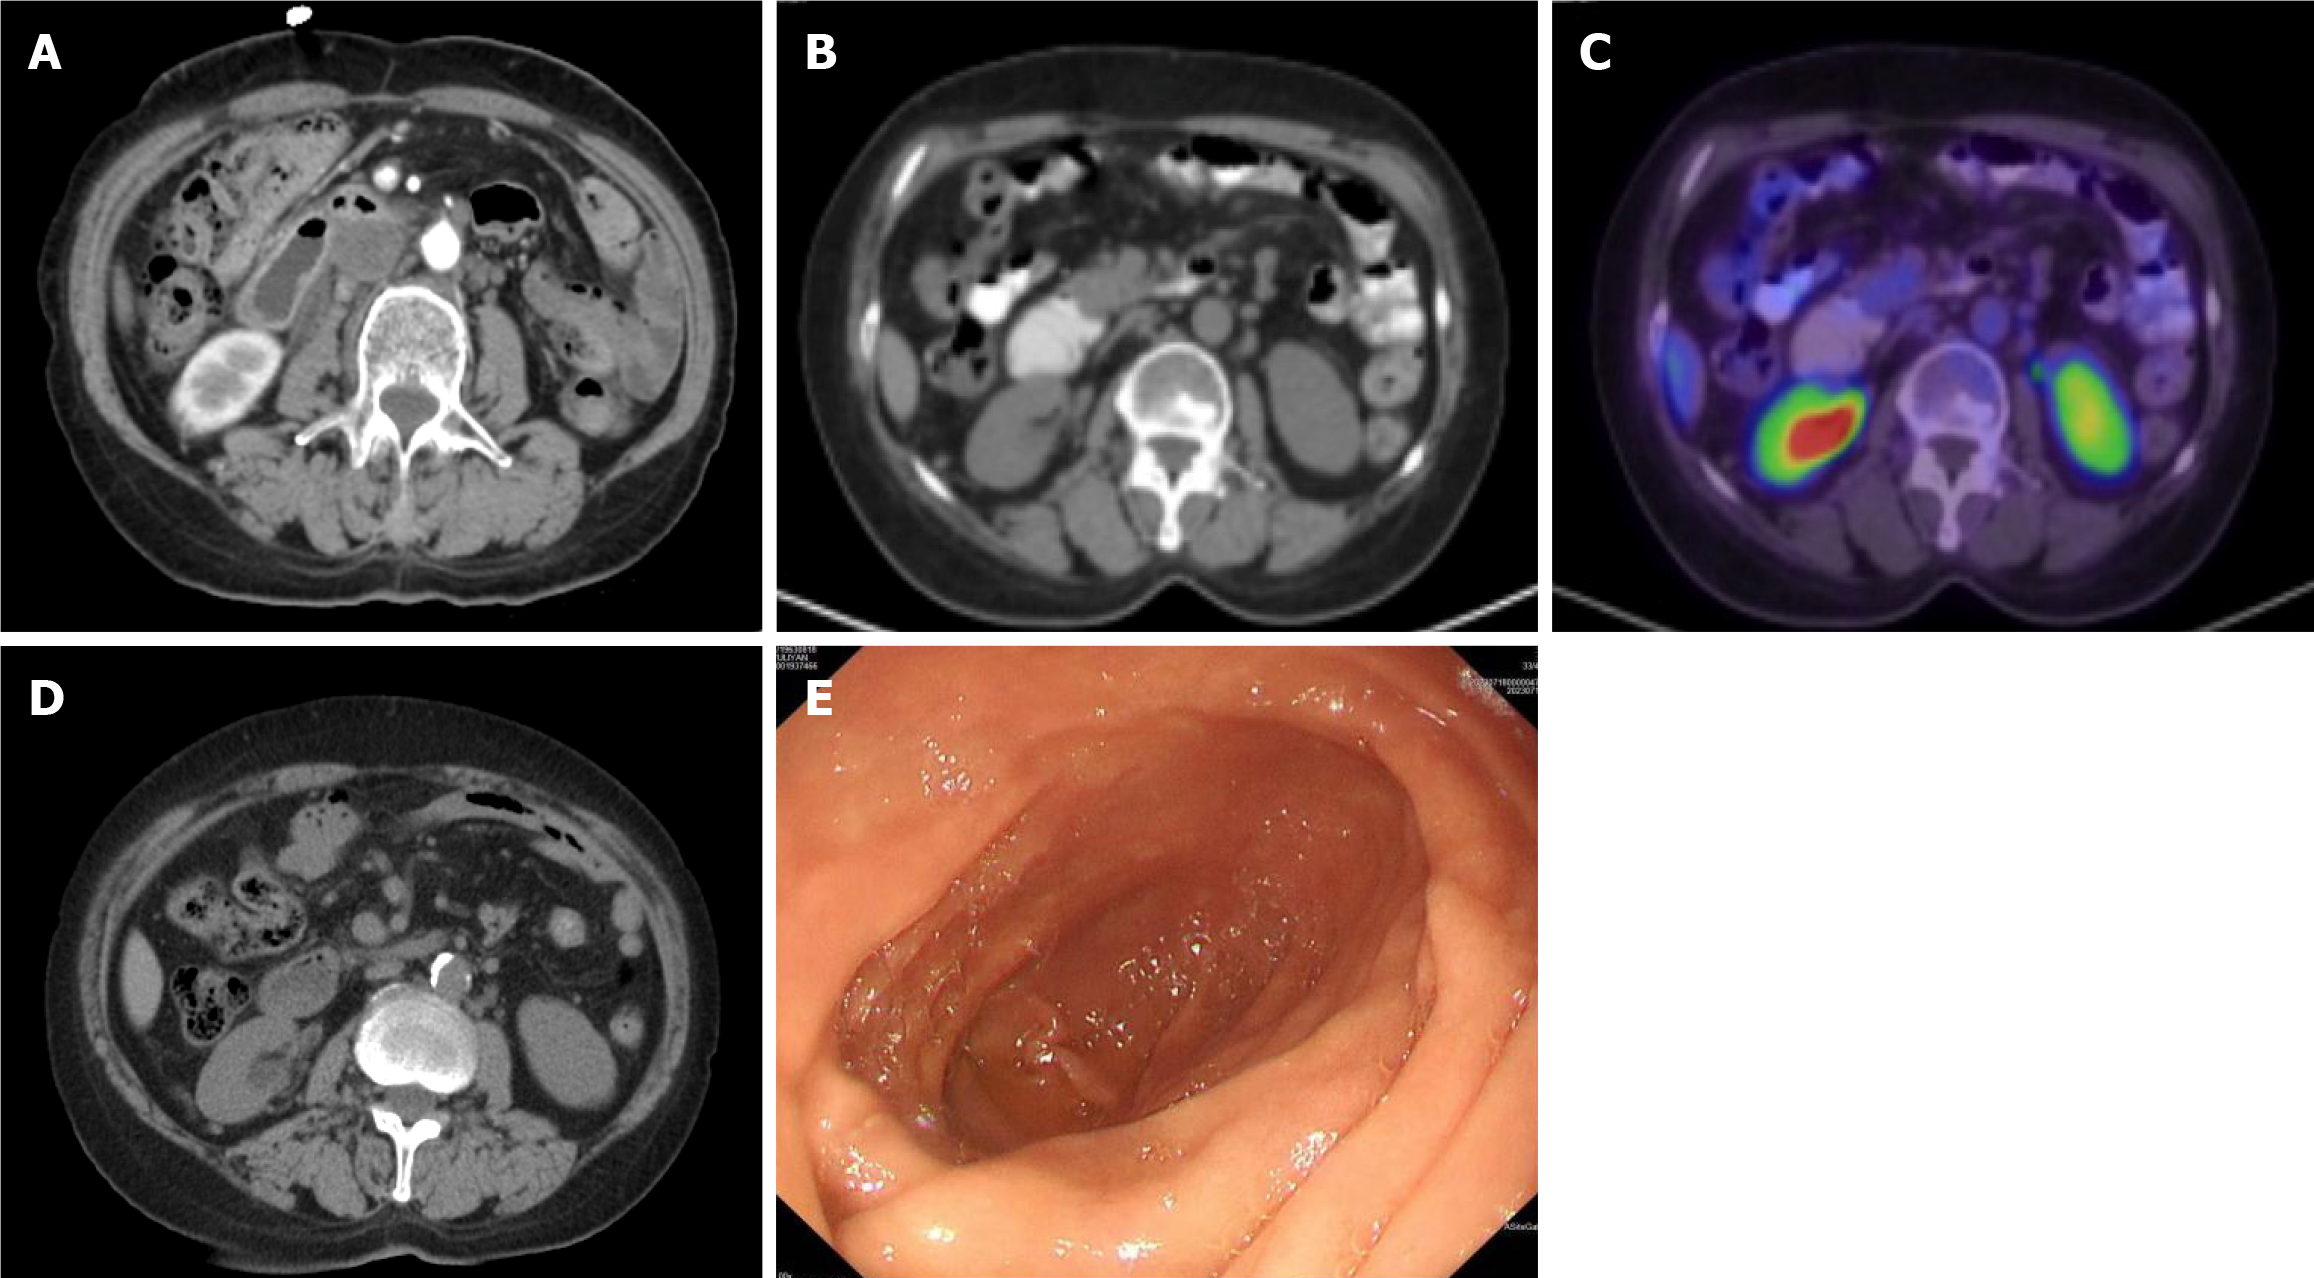

Figure 3 After receiving pembrolizumab.

A: After receiving 2 cycles of pembrolizumab. computed tomography (CT) showed that the duodenal mass was significantly smaller than before; B and C: After receiving pembrolizumab for 2 years. Positron emission tomography/CT showed low density at the lateral pancreatic head attached to the duodenum and no increase in metabolism; D and E: After receiving 4 years of pembrolizumab. CT revealed no thickening of the duodenal wall (D). Upper gastrointestinal endoscopy showed smooth mucosa in the descending duodenum (E).